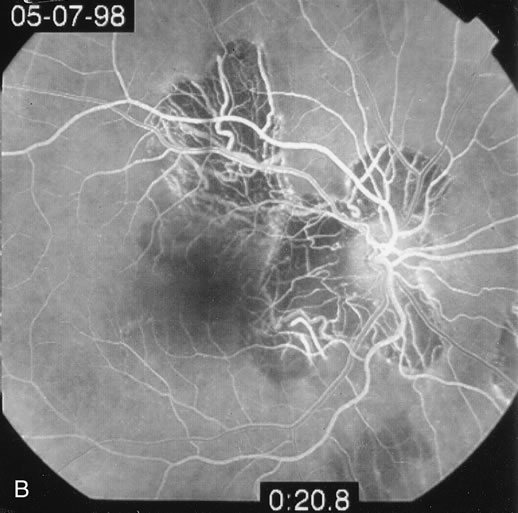

Fluorescein

The classic findings in the acute cases are lesions of variable size that are hypofluorescent in the early phase of the fluorescein angiogram. In the late phases of the angiogram there is hyperfluorescence of the lesions. In the late phases, there also may be leakage from the disc as well, and there also may be staining of the retinal vessels because of the vasculitis. With resolution of the disease, there still may be a mottled pattern of fluorescence correlating with the areas of pigment clumping and pigment atrophy (Fig. 8).

Fig. 8. A. Early fundus angiogram showing hypofluorescence of the acute posterior multifocal placoid pigment epitheliopathy (APMPPE) lesions. B. Later stage of the angiogram showing staining of the APMPPE lesions.